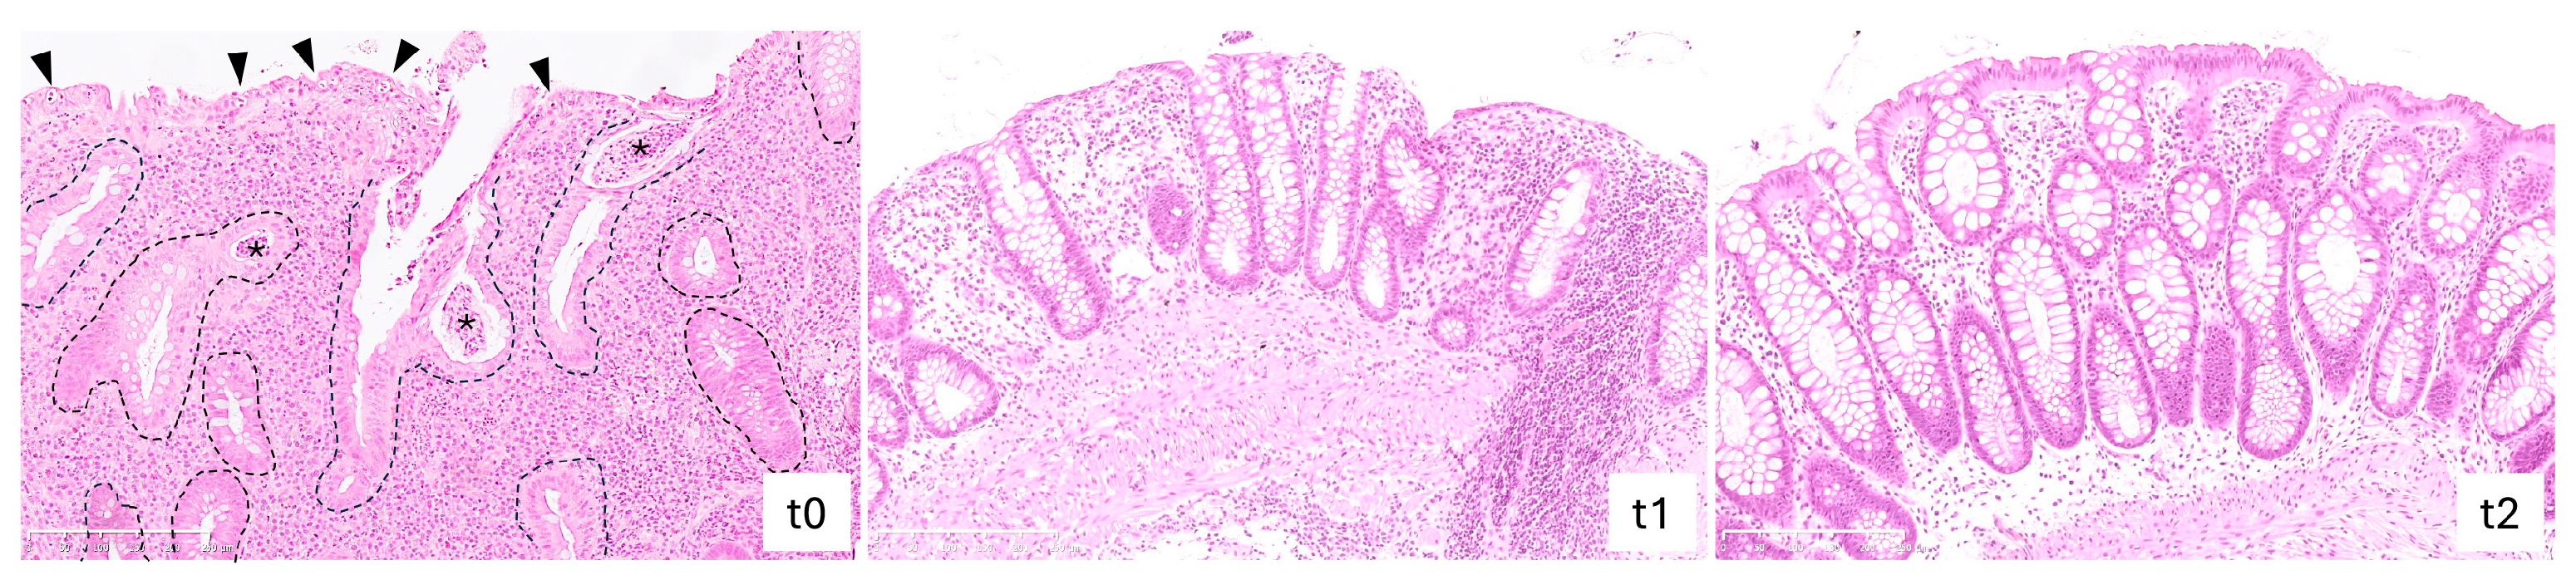

2.4. Vedolizumab Treatment Reduced Histological Grading of Inflammatory Activity in IBD